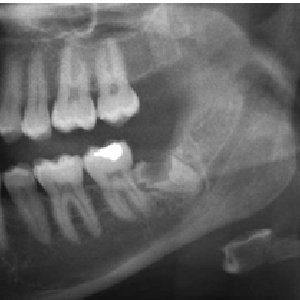

العصب السنخيalveolar nerve يكون احيانا في وضع قريب جدا من ذروة جذور اضراس العقل

الاضراس السفلية تكون في بعض الاحيان قيبة جدا ومتداخل مع قناة العصب السنخي

الاضراس العليا تكون احيانا في وضع قريب جدا من الجيوب في الفك العلوي واحيانا تكون ملاصقة

قدر هذه المريضة ان اضراس العقل السفلية قريبة جدا من مجرى العصب السنخي

واضراس العقل العليا قريبة جدا من جيوب الفك العلوي